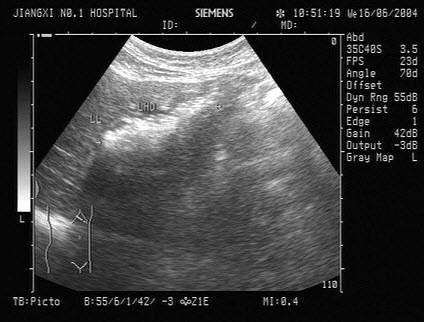

103、单项选择题

男,48岁,上腹胀痛,纳差,血吸虫病多年。结合超声声像图,诊断为()

A.血吸虫肝纤维化

B.脂肪肝

C.细菌性肝脓疡

D.肝豆状核变性

E.肝炎